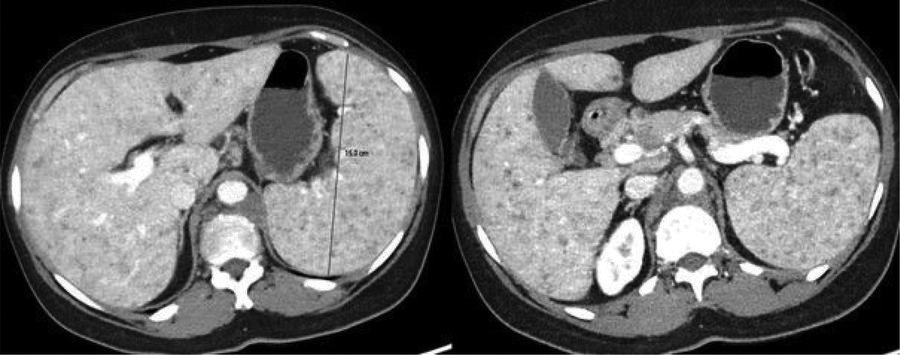

Figure 1

Axial contrast-enhanced CT